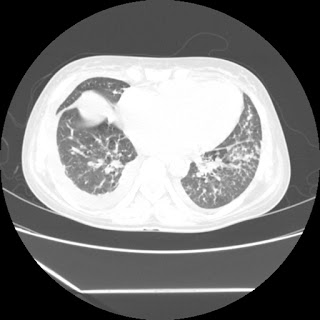

(HRCT)CT-Scan investigation done on 19Aug15 :

Series2